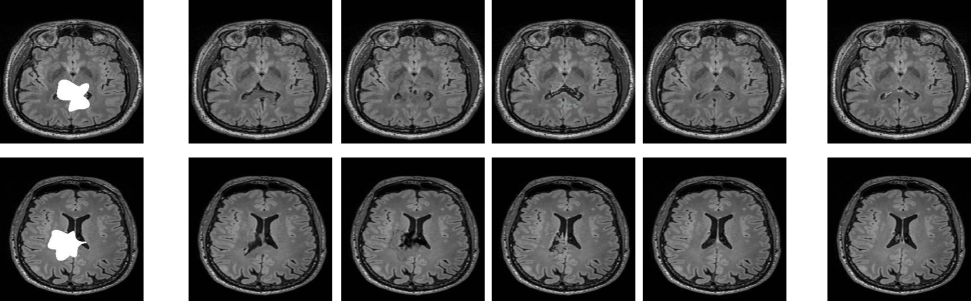

Refer to captionInputpix2pixMedGANGated-ConvipA-MedGANTarget

Fig. 4: Qualitative comparison of inpainting for arbitrary-shaped regions with ( ) showing the advantages of ipA-MedGAN.

The second set of experiments focuses on the inpainting of arbitrary shaped regions. To achieve this, a set of 100 random masks, whose size range from 1.36% to 5.46% of the total image area, were utilized to create the input MR scans y𝑦y. For validation, a different set of 50 masks, whose size range from 1.66% to 4.56%, was utilized to test the generalization capability of the proposed framework. To evaluate the performance of ipA-MedGAN, qualitative and quantitative comparisons were conducted against the gated convolutions inpainting framework (Gated-Conv) [10] and other image-translation approaches, i.e. pix2pix [13] and MedGAN [18].

In Fig. 4 and Table I (b), the qualitative and quantitative results for arbitrary inpainting of MR are displayed, respectively. The gated convolution framework produced inpainting regions with altered textural and anatomical characteristics when compared to the target images. This was also indicated quantitatively by the inferior scores in Table I (b). Generative image-to-image translation approaches resulted in better qualitative results that fit more homogeneously with the surrounding regions. However, the inpainted images produced by pix2pix depicted blurry and unrealistic textures. On the other hand, results by MedGAN contained distinct visual tilting artifacts. The proposed ipA-MedGAN framework resulted in more coherent and artifact-free inpainted regions which closely matche the desired target images. This was also reflected quantitatively with the scores in Table I (b). More notably, the significantly improved UQI and MSE scores. Compared to other traditional inpainting frameworks such as gated convolutions and GLCIC, this comes with the additional benefit of not requiring prior localization of the regions of interest during training.